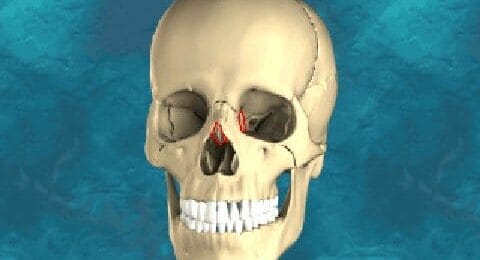

Zeefbeen

De zeefbeendelen (pars os ethmoideus) bevinden zich tus...

Traanbeen

De traanbeentjes zijn twee van de kleinste botjes in he...